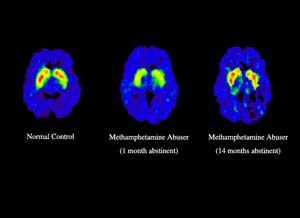

Now luckily for meth users they regrow; however the bad news is they take quite sometime and for months meth users are feeling the absence of this reward because the reward center of the brain has essentially been damaged. Other areas of the brain are also effected. This is an MRI of the human brain done here at UCLA and this shows the judgment center of the brain in the prefrontal cortex. This is the brain of a meth user who's about five days sober and this blue area represents a reduction in normal activity, a reduction in blood flow. In essence, this part of the brain is shut off and for meth users who are in early recovery, they really don't have the ability to make good decisions.

You have this sort of worst-case scenario. You have a brain that is not producing reward, you're having a lotta craving because you want to feel better, and you have the part of the brain that controls judgment not working, and so individuals do stupid things that end up with them relapsing and going back to using. It's a wonder any meth users ever get better, but in fact they do.